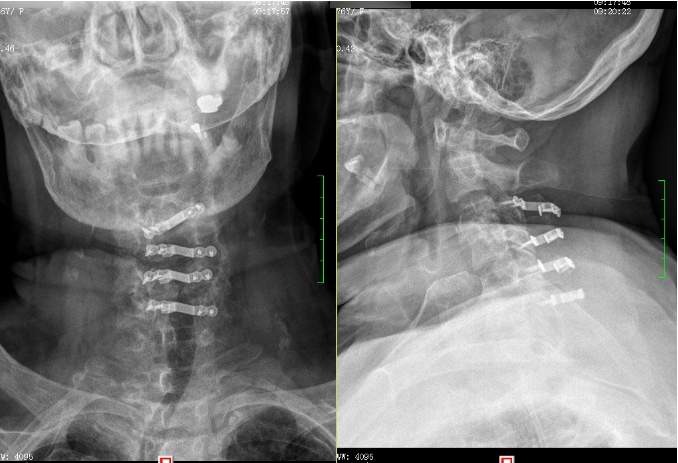

经过充分的术前准备,惠亚医院脊柱外科团队在多学科协作下,成功为刘奶奶实施了颈椎经后路单开门椎管扩大成形手术,全程仅用时1时半,出血50毫升。术后,刘奶奶的四肢肌力恢复良好,术后第5天就能在家人的搀扶下下床活动。

▲术后X射线影像